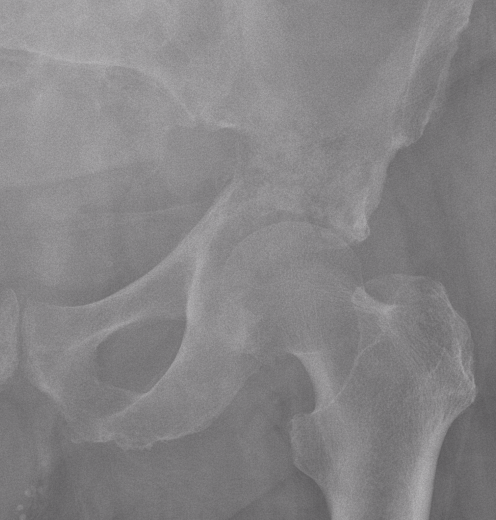

Location

Extremities 45%

- medullary canal metaphysis long bones

- proximal femur

Axial skeleton 31%

- 20% pelvis

Pelvis

Issues

- low grade uncommon

- wide resection difficult

Wide resection

- hemipelvectomy

- hind quarter amputation (1% mortality)